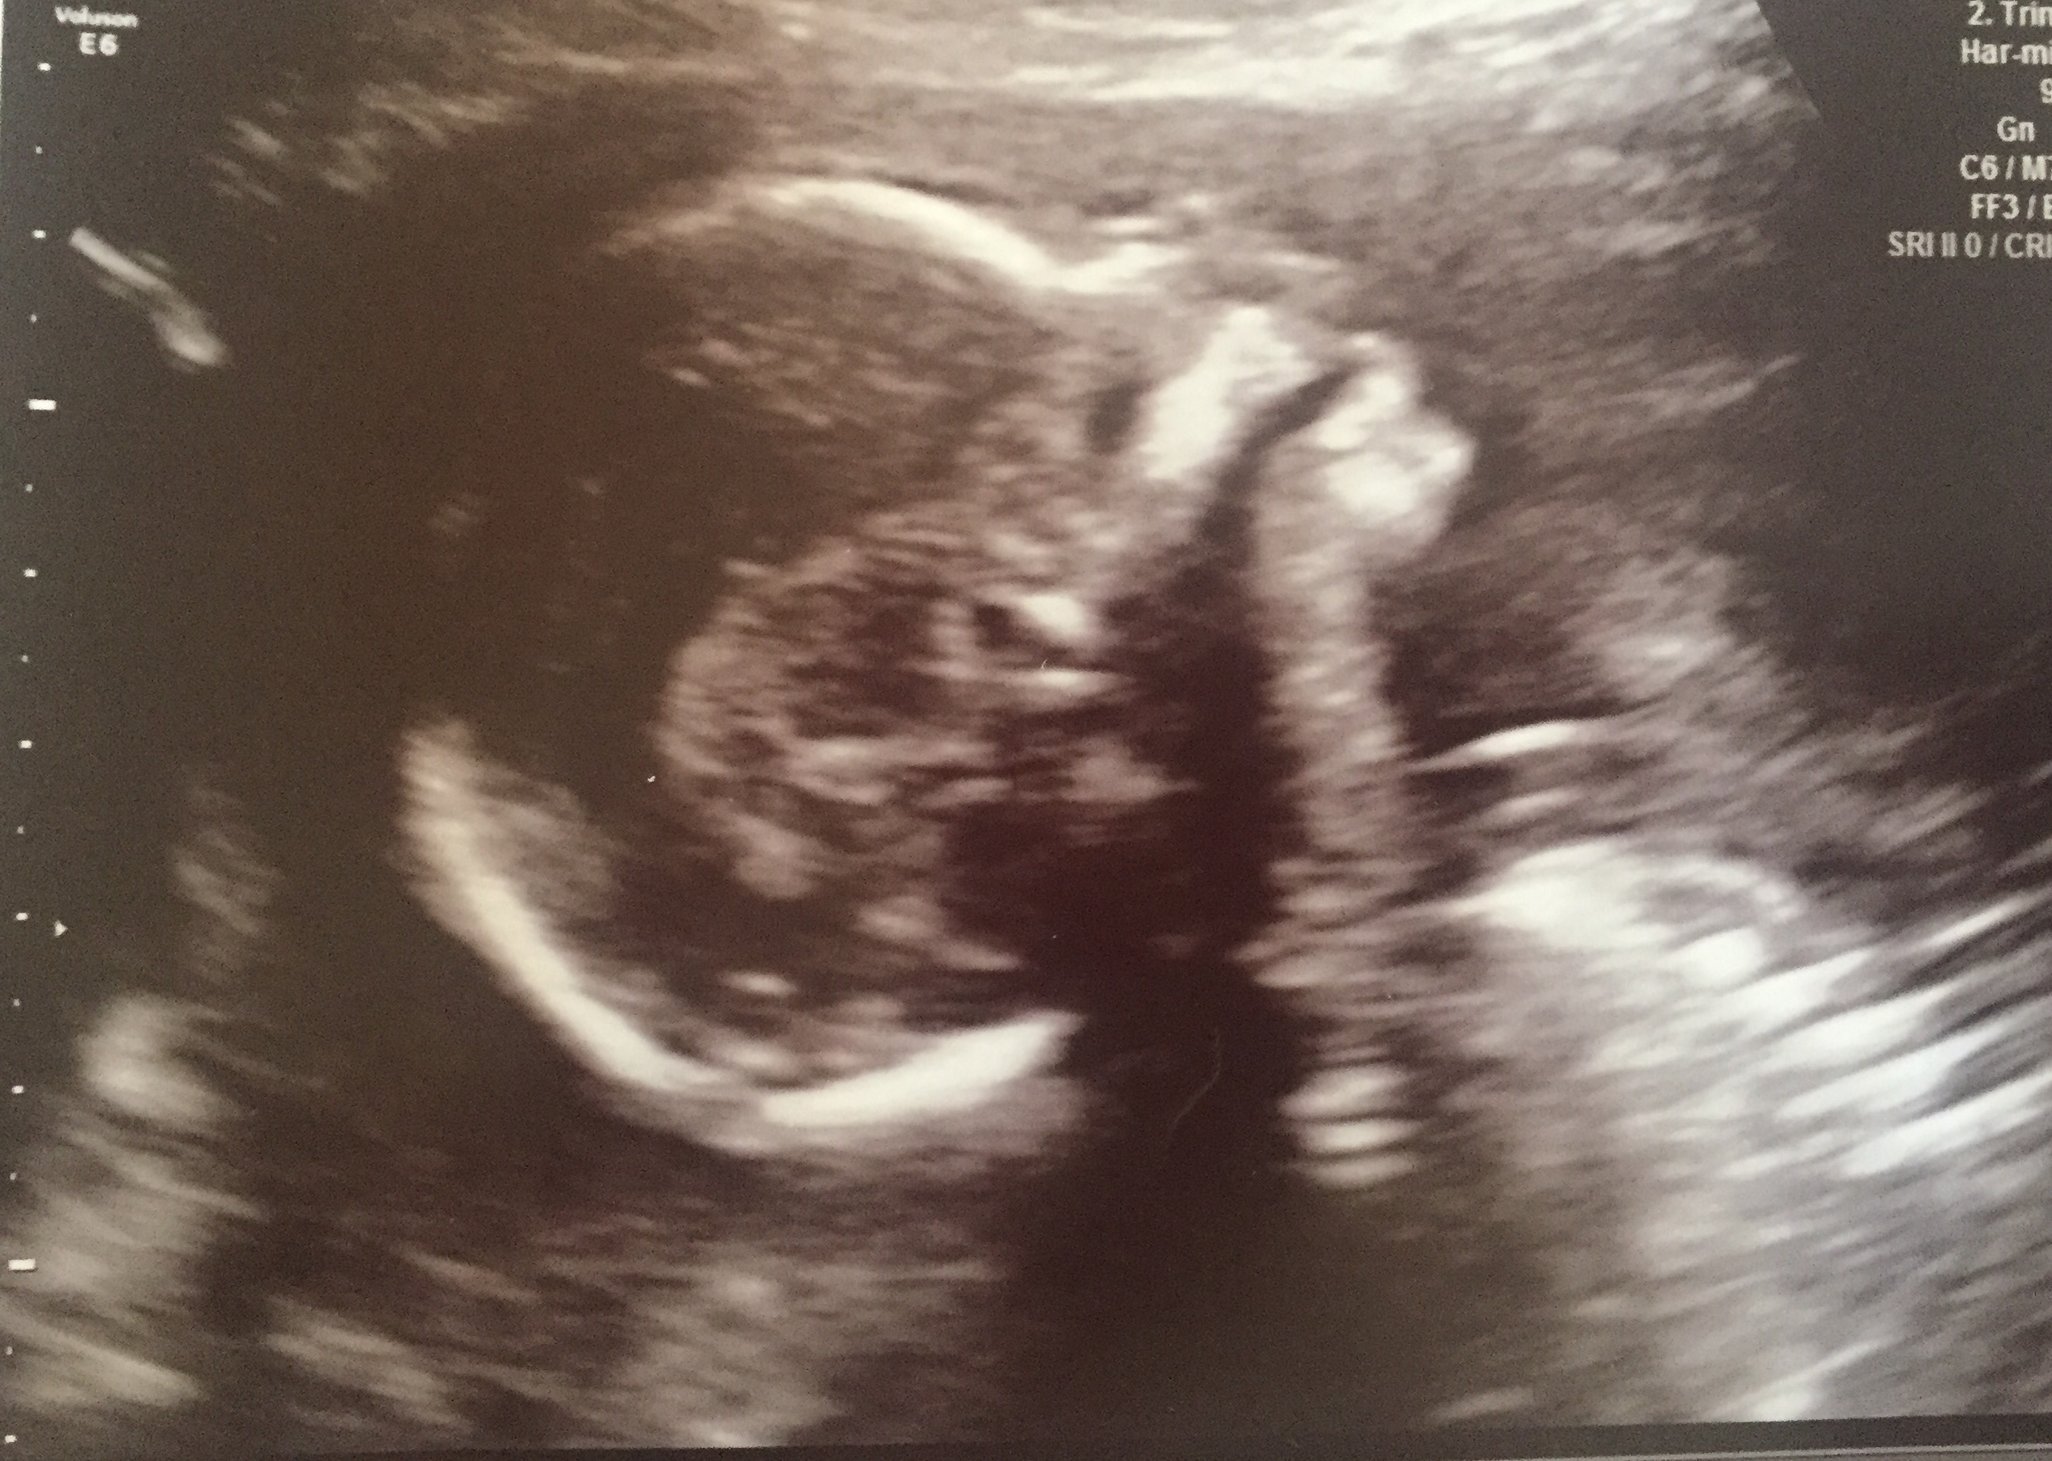

Symptoms/Rants/Raves? Raving!!! I am so happy to hit the 1/2 way point and that we had a perfect A/S today! I'm "aw-ING" and attaching a picture of my perfect peanut! We are team green and baby stayed true to that & wouldn't cooperate with the dr to show what it is!! I was happy bc I was afraid they'd slip & tell us